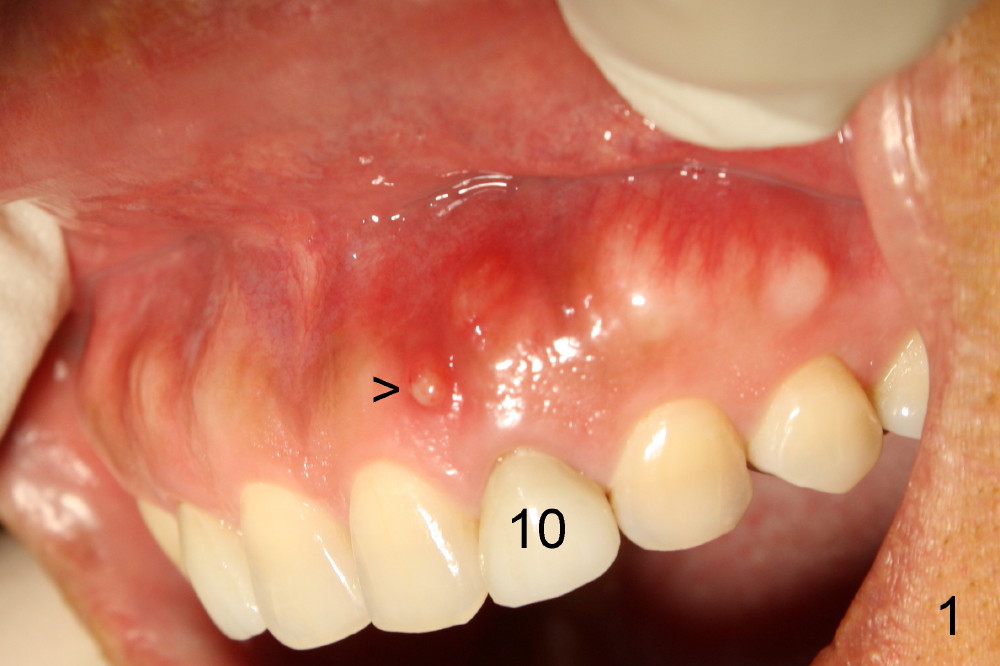

A 49-year-old lady has failed endo on the upper left lateral incisor (Fig.1,2). A gutta percha inserted to the buccal fistula (Fig.1 >) shows a mesial defect (Fig.2<). There is a large buccal apical defect, corresponding to the lesion shown in Fig.2 *, when the affected tooth is extracted. After thorough debridement and Clindamycin soaking, osteotomy is initiated in the palatal wall of the socket. Demineralized freeze dry cancellous bone graft is placed in the buccal defect. A 4x20 mm gingiva-level tapered implant is placed with insertion torque 50 Ncm (Fig.3). A 3x5 mm 20 ° offset abutment is inserted and cemented (Fig.4,5). A retentive groove is prepared on the abutment and the underlying implant; chamfer margin placed on the implant (Fig.4,5). A provisional is fabricated and cemented temporarily (Fig.6,7). Excess cement is removed, followed by removal of gingival retraction cord. There is no contact in centric and non-centric occlusion.

Within one week, the infection resolves (Fig.8,9).